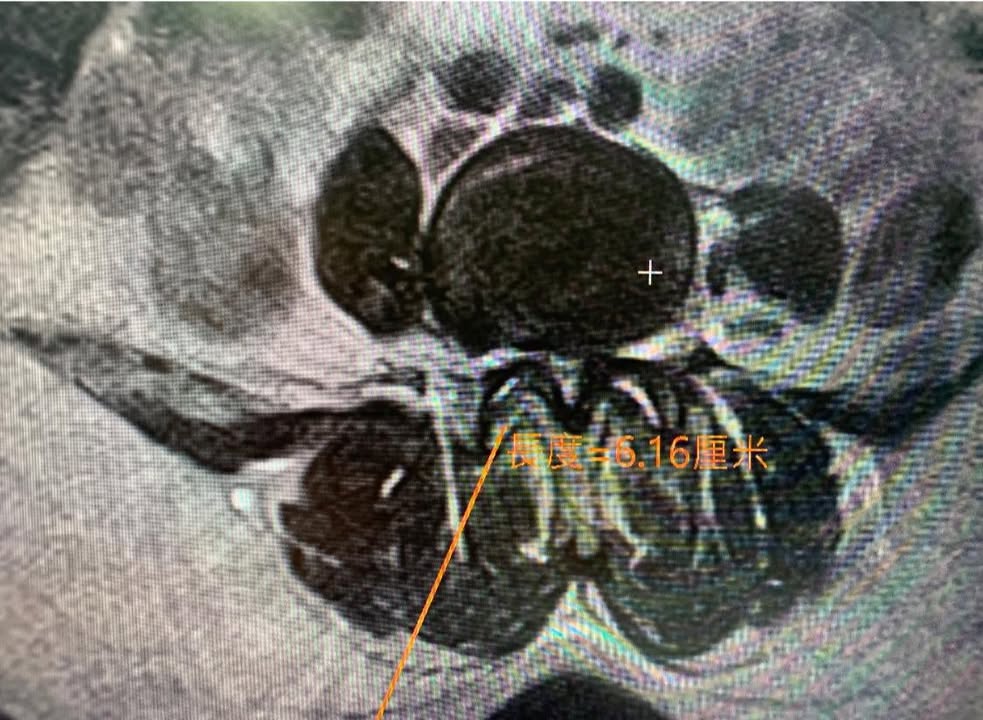

七十歲的李阿姨說雲林北港的蒜農,再來診之前已經大痛快三個月,腳非常的麻痛,上下樓梯也非常痛,走路最嚴重的時候沒有辦法走超過10分鐘,先去當地的復健科診所拍攝片子,就發現腰椎有滑脫的現象,做了一陣子的復健效果仍然不如預期,才去當地的大醫院拍攝核磁共振,更發現椎管狹窄,壓迫雙側神經跟根,因為復健的效果不理想所以神經外科醫生建議開刀治療,女兒介紹特別從雲林北上就醫

診斷:L4 on L5第一度滑脫

L5S1椎間孔第二度狹窄